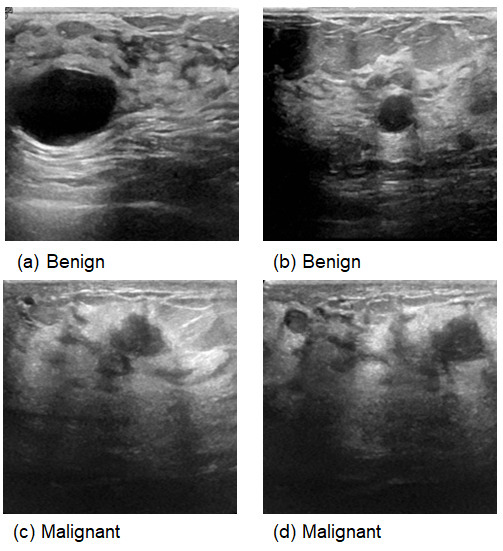

Breast Ultrasound Images Dataset: [35] Available on Kaggle, this dataset contains 971 breast ultrasound images originally categorized into three classes: normal, benign, and malignant, with corresponding labels (0, 1, and 2). For the purposes of this study, the “normal” images were excluded, and only benign and malignant images were used for classification. The dataset thus contains two classes (benign = 0, malignant = 1), as reflected in all tables and analyses in the manuscript. This preprocessing ensures a focused evaluation of the model for distinguishing between benign and malignant findings.

This comprehensive approach of utilizing datasets from multiple imaging modalities shown in Figure 1, Figure 2, Figure 3 and Figure 4 and summarized in Table 1, including mammography, ultrasound, MRI, and histopathological images, ensures robust model validation and enhances the system’s capacity to accurately classify benign and malignant findings. By leveraging these diverse datasets, we aim to develop a more generalizable and effective breast cancer classification system.

Figure 3. Samples from Ultrasound images.